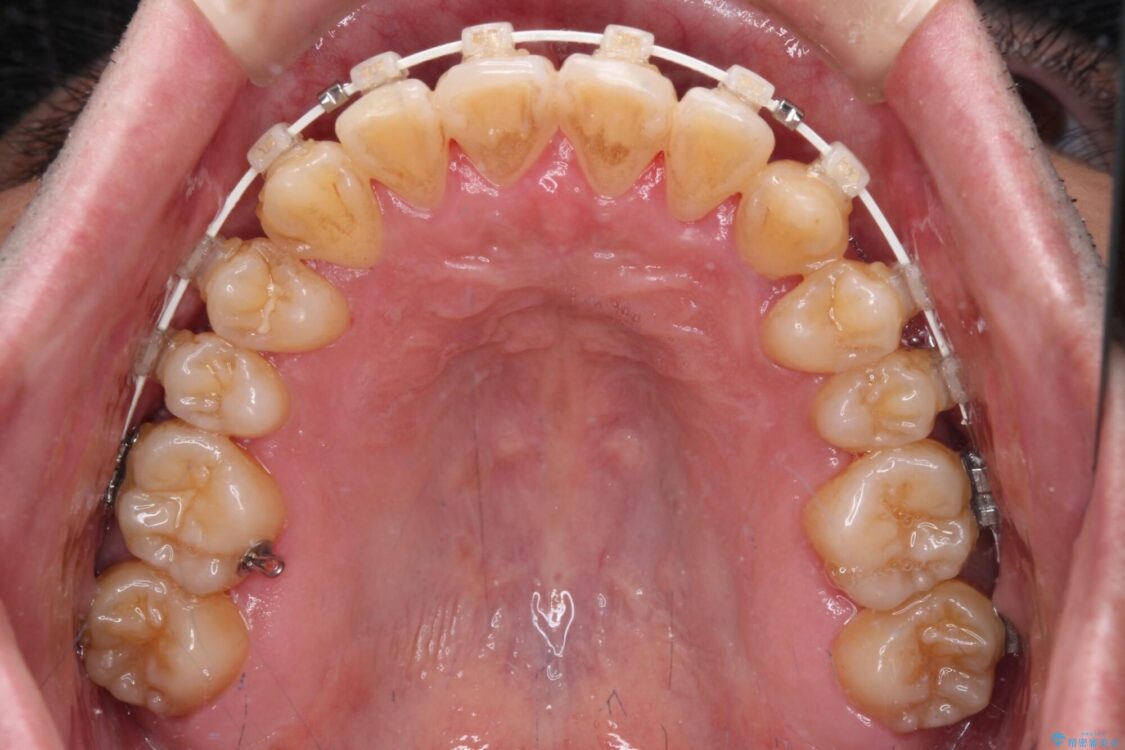

治療途中

• 八重歯とクロスバイト 目立たないワイヤー装置で矯正治療 治療途中画像

マウスピース矯正での自己管理には自信がないとのことで、ワイヤー装置による矯正治療を行うこととしました。

クロスバイトは、治療の過程で咬み合わせが大きく変化する期間があり、食事が取りにくくなってしまいます。

また、装置が対合歯と咬み合ってしまい、頻繁に脱落するなど、色々と面倒なことがあり、治療がスムーズに進まないことがあります。